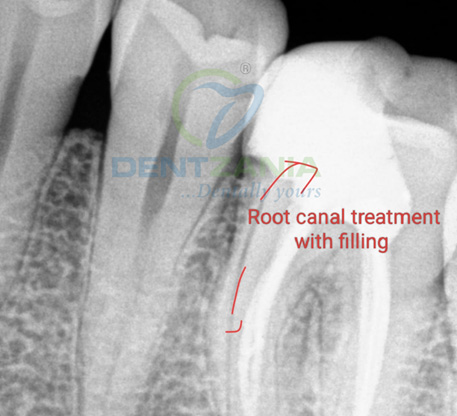

4. Shaping & Filling the Root Canals

The infected pulp is removed and the tooth is filled with root filling

If the nerve of a tooth has become decayed or infected, a Root Canal may save the tooth itself whilst removing the problematic root. The nerve part of the tooth, along with the pulp (living tissue inside the tooth) and any bacteria or decay present is removed; then the tooth is sealed with special root-filling cement all the way to the tip of the root. This will save your tooth once the root is filled and sealed properly to the very apex; and it gets rid of the painful soft tissue and leaves a hard shell. A dental crown is then fitted to ensure the tooth has full functionality within your mouth.

Sometimes there may be no symptoms present. The Root Canal Procedure may need 1 – 2 appointments , depending on the patient and the state of the tooth. At dentzania , with our expert team and latest technology , experience painless single visit root canals and give your teeth a new life ! There is no pain in modern dentistry, and the whole area will be completely numbed by local anaesthetic so you will be comfortable. If necessary any tooth decay is also be removed using special dental instruments. After the tooth has been thoroughly cleaned, it is sealed with either a permanent filling or a temporary filling should additional appointments be needed. At the next appointment, (about a week later), the roots and inside cavity of the tooth are sealed and filled. A filling is placed on top of the tooth to cover the opening and any teeth that have root canal treatment are then fitted with a dental crown to protect the tooth and restore it to its full function.